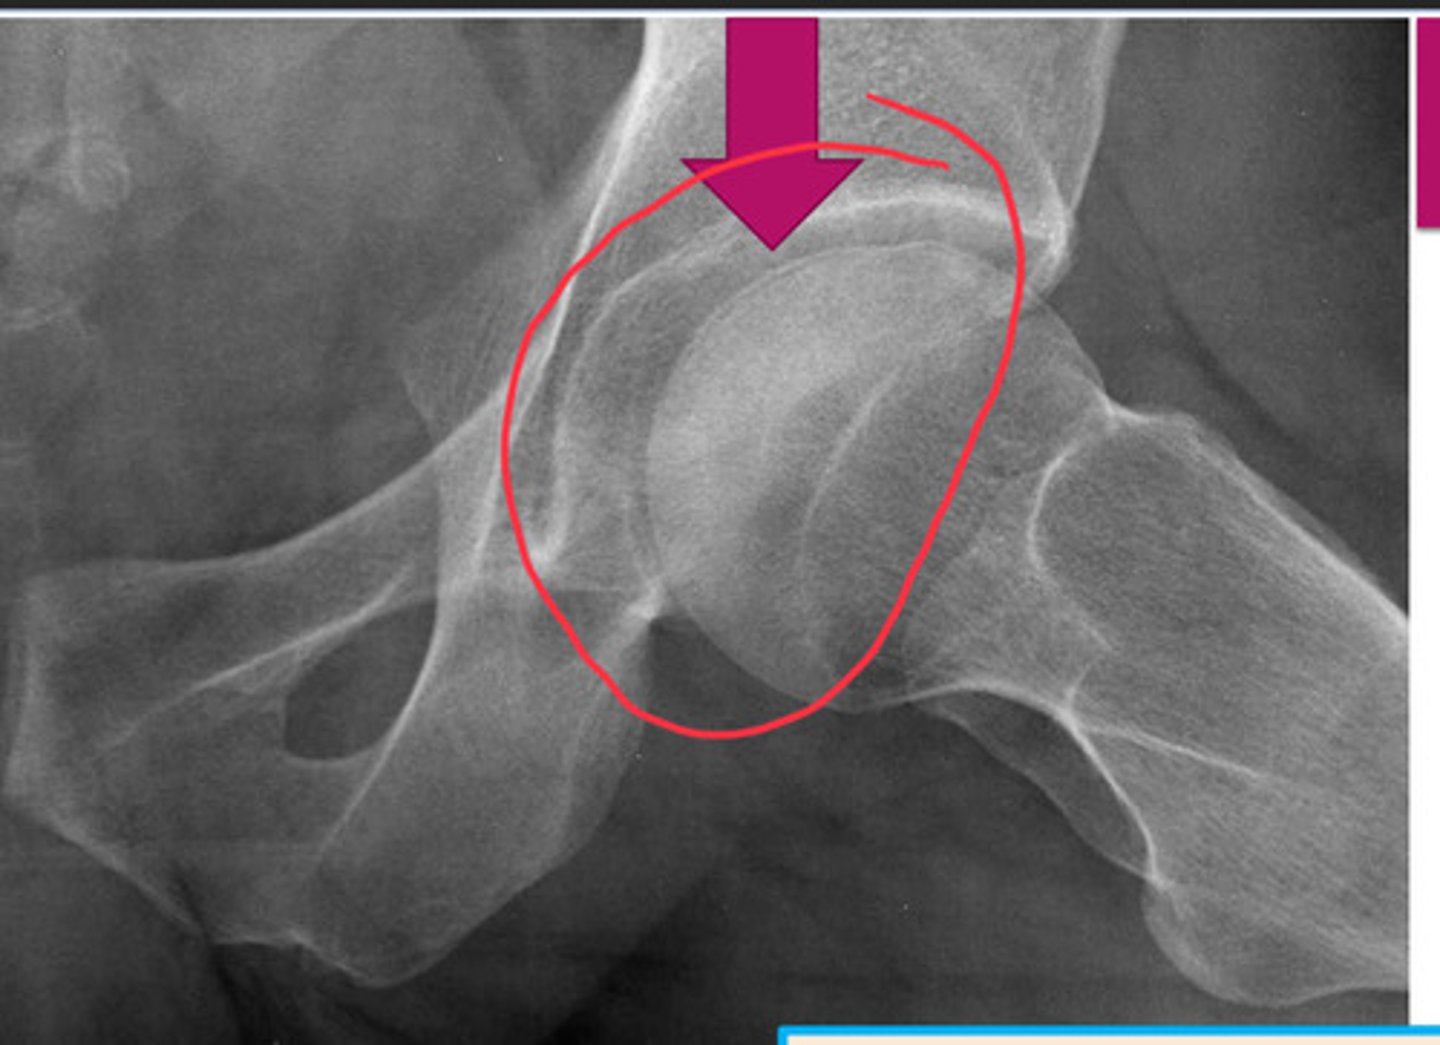

AVN of bone

poor blood supply --> cell death --> collapse of bone

how does AVN appear in later stages?

INCREASED DENSITY

where does AVN m/c occur?

scaphoid in wrist, femoral head, humeral head

what is the most sensitive modality for detecting AVN?

MRI

causes of AVN

Intravasc: sickle cell & PCV

Vasc: vasculitis (lupus & radiation induced)

Extravasc: trauma (frx)

Idiopathic: exogenous steroids, cushings, legg-calve-perthe disease (delayed bone growth by time child is 2 is 1st presentation)

crescent sign

occurs when surface of articular surface is flattening (DO NOT MISS! PRECURSOR TO WORSENING DISEASE!)

pictured: AVN of femoral head